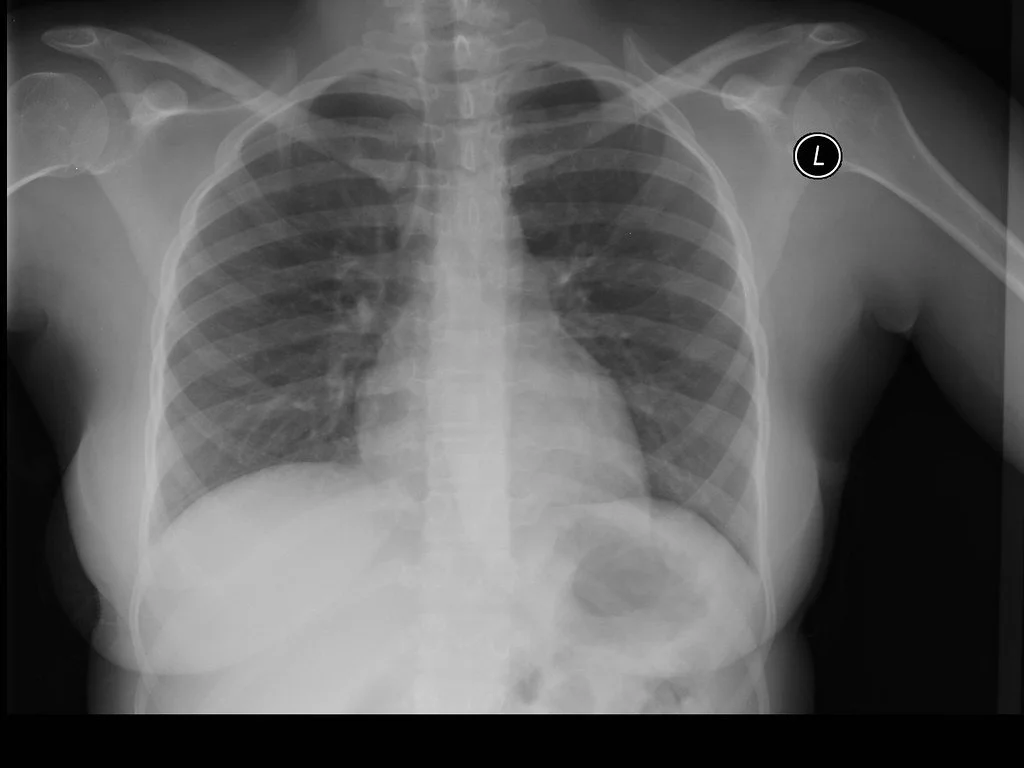

Chest imaging is one of the most frequently used diagnostic tools in emergency and acute care settings. When used thoughtfully, it can rapidly narrow a differential diagnosis, guide urgent decision-making, and identify life-threatening pathology. When used indiscriminately, it can also create false reassurance or lead to unnecessary downstream testing.

This session focuses on a practical, clinically grounded approach to chest imaging with an emphasis on how and when to use chest X-ray, ultrasound, and CT effectively.

Chest imaging is most valuable in high-risk clinical scenarios such as hypoxia, respiratory distress, trauma, suspected infection, chest pain with concerning features, and shock. Understanding which clinical presentations require immediate imaging and which can be evaluated conservatively is a critical skill for frontline clinicians.

While chest X-ray is often the first imaging modality obtained, it has important limitations. Vascular pathology such as pulmonary embolism, aortic dissection, or myocardial infarction may not be visible on plain radiographs. Recognizing what chest X-ray can and cannot show helps prevent missed diagnoses.

A structured approach to reading chest imaging reduces error. This presentation emphasizes consistent interpretation methods, including evaluating the mediastinum, heart, lungs, diaphragm, pleura, chest wall, and soft tissues in a reproducible sequence.